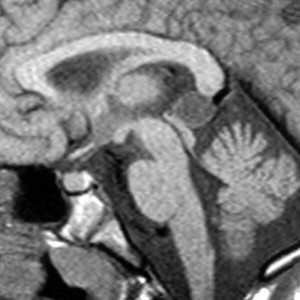

(Слева) Бесконтрастная КТ, проводимая в рамках рутинного наблюдения за пациентом в динамике, аксиальный срез: у юноши 14 лет через два месяца после эвакуации субдуральной гематомы, образовавшейся вследствие футбольной травмы, определяется дефект черепа и посттравматическая энцефаломаляци.

(Справа) Два года спустя тот же пациент стал наблюдать постепенное увеличение «шишки» на голове. При повторной бесконтрастной КТ определяется, что края дефекта черепа выступает наружу, а через сам дефект выпячивается объемное образование с плотностью, подобной ликвору, которое располагается под сухожильным шлемом.

(Слева) КТ, костное окно, аксиальный срез: отмечается, что кортикальный слой краев дефекта черепа хорошо выражен. Обратите внимание на фестончатость наружной пластинки кости свода черепа.

(Справа) КТ, костный режим, 3D реконструкция в режиме оттененных поверхностей: визуализируется расширенный дефект черепа с фестончатыми краями. По поводу данного «растущего» перелома черепа с лептоменингеальной кистой было проведено оперативное лечение.